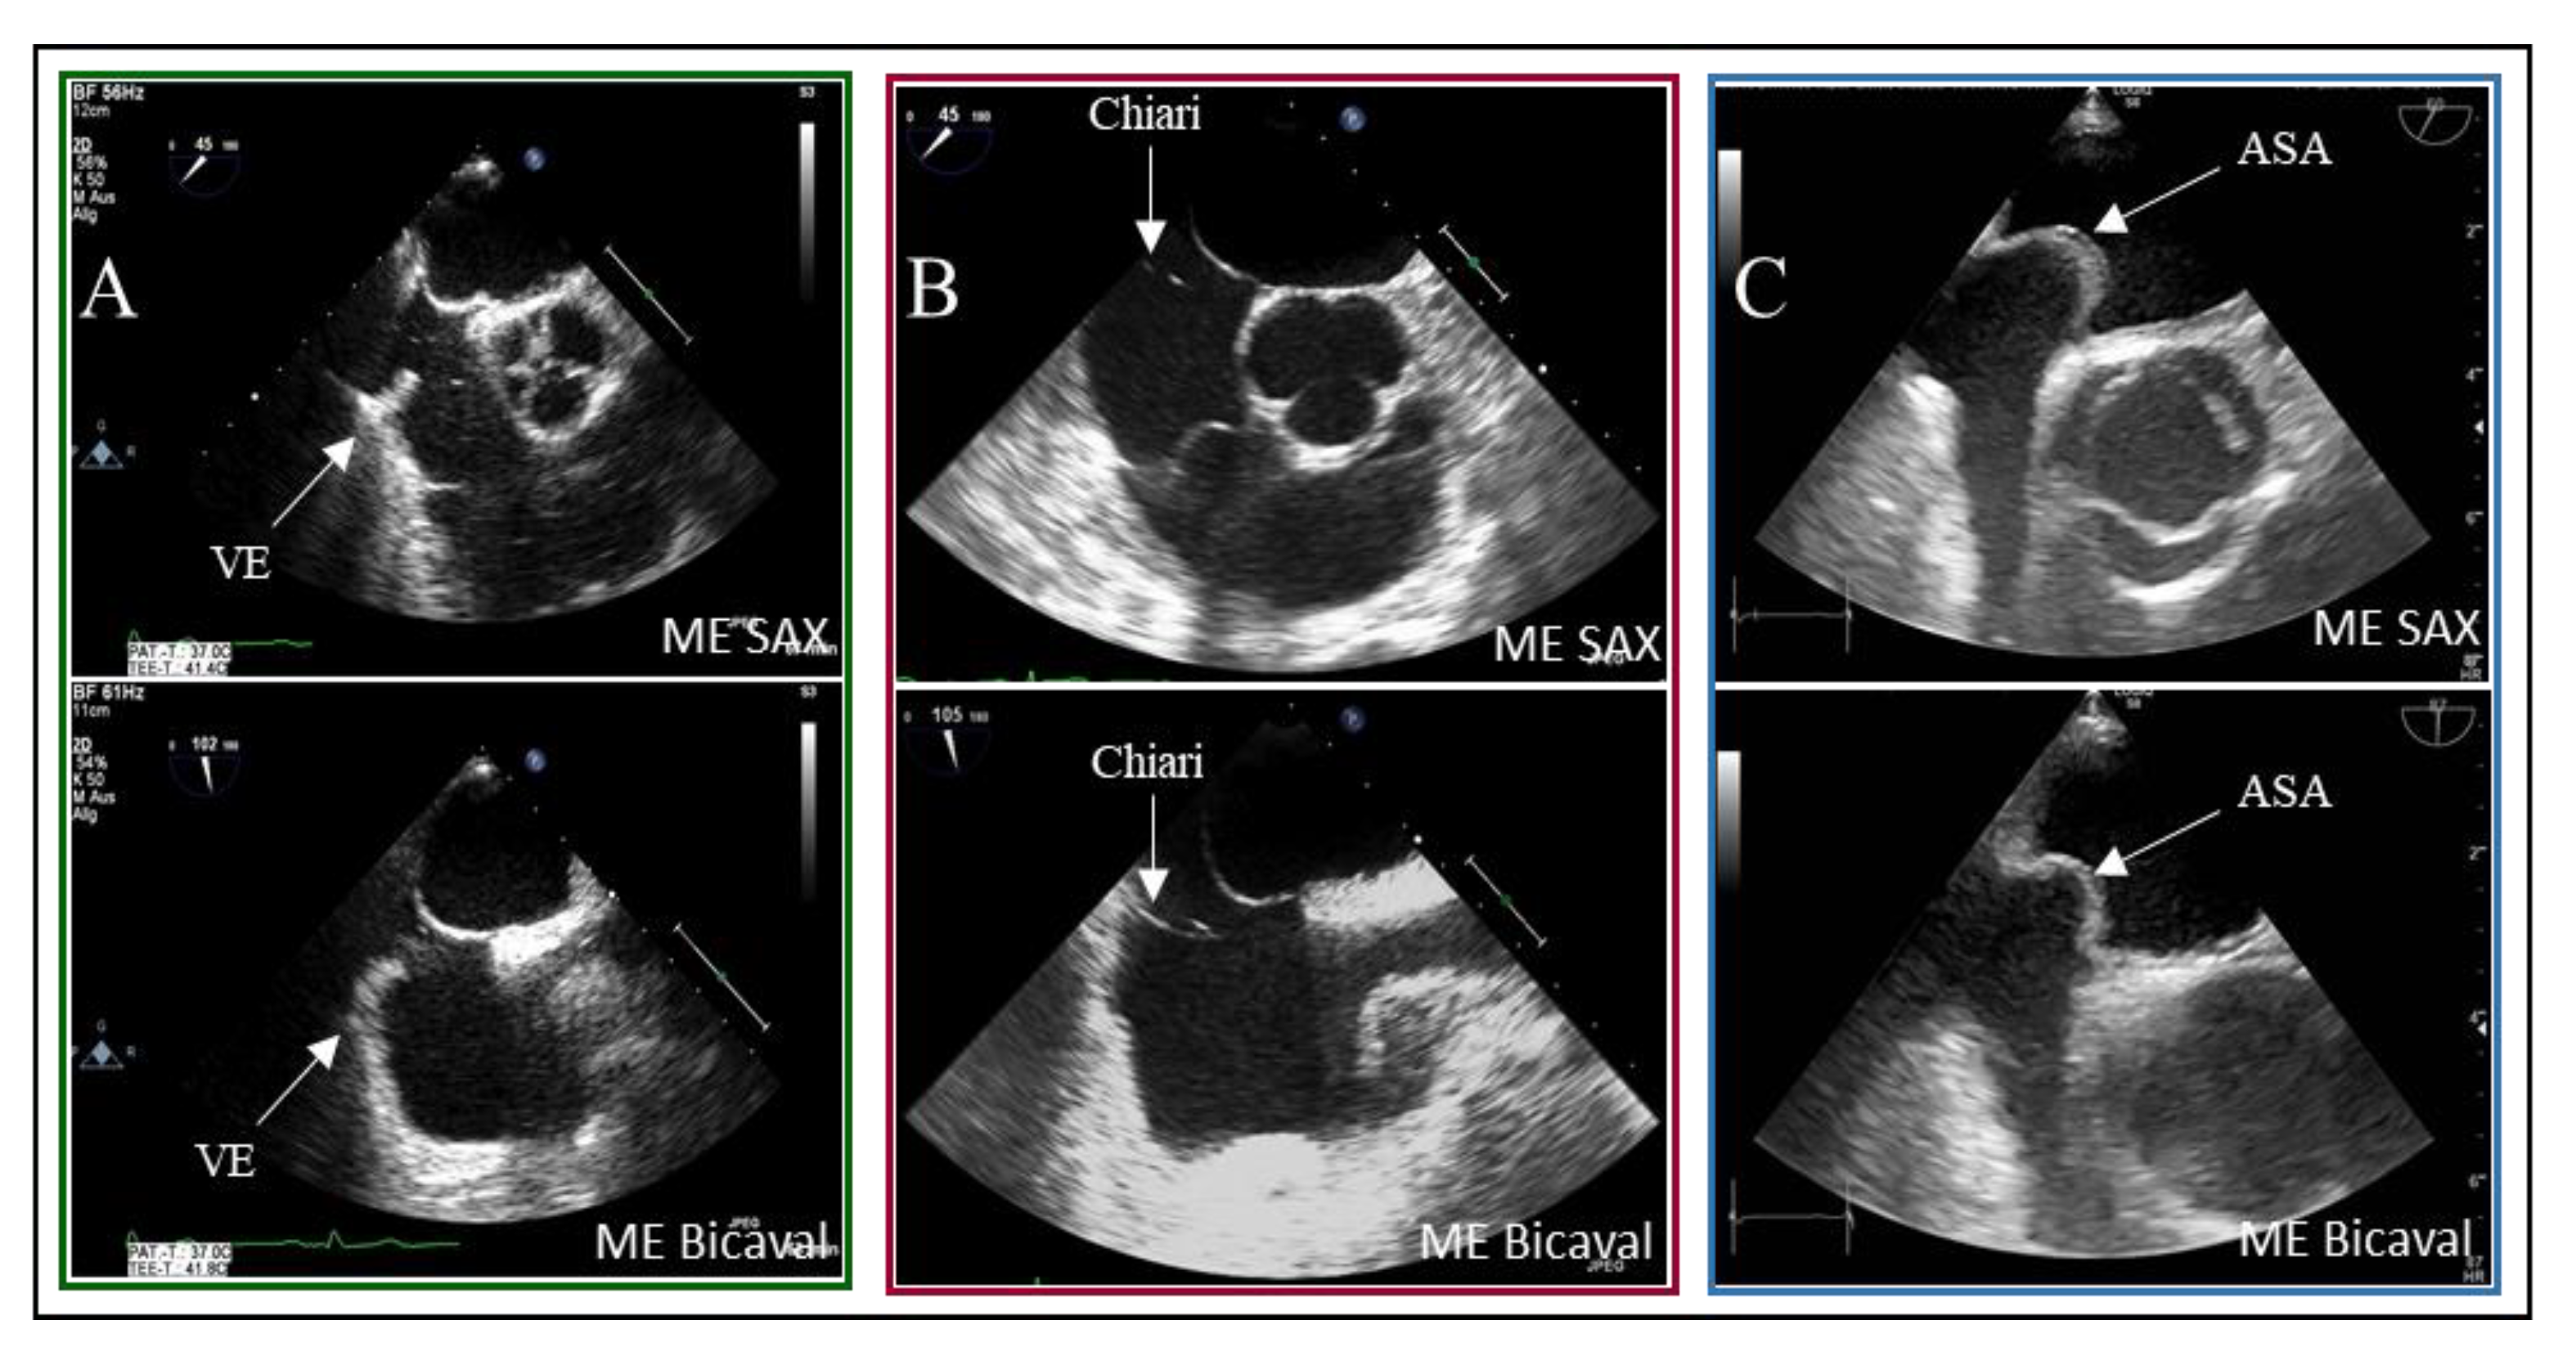

Background: Transesophageal echocardiography (TEE) is regarded as the gold standard for diagnosing patent foramen ovale (PFO). However, the occurrence of false positive PFO diagnoses is common in clinical practice, which may lead to unnecessary percutaneous interventions, as PFO occluders can only be placed when PFO presence is unequivocally confirmed. Various medical societies recommend a systematic protocol for the thorough assessment of the interatrial septum. Purpose: This study aimed to evaluate the incidence of false positive PFO diagnoses and analyze the underlying causes of misdiagnosis by comparing imaging data. Methods: In this retrospective observational study, we included 346 patients who were diagnosed with PFO following a cryptogenic ischemic stroke from January 2012 to December 2021. We first assessed the incidence of false positive PFO diagnoses. Subsequently, we compared stored imaging sequences from the screening TEE examinations with recommended diagnostic protocols outlined in European and American guidelines, identifying sources of diagnostic error. Results: The patient cohorts were divided into two groups: Group A consisted of 20 patients (5.8%) with PFO misdiagnoses, while Group B included 326 patients (94.2%) with accurate PFO occlusions. Our review of guideline compliance revealed that imaging planes in the mid-esophagus were used significantly more frequently than modified transgastric probe positions in the upper esophagus (71-96% vs. 1-2%). Three-dimensional imaging of the interatrial septum (IAS) was rarely utilized (0-3%), and the stepwise enlargement of the transducer angle in 15° increments was only partially documented. Comparisons between the two subgroups indicated reduced utilization of the bicaval viewing plane in the middle esophagus for the false positive group (Group A: 50% vs. Group B: 87%, p<0.001). The bubble test was performed in 80% of the misdiagnosis group using the short axis view, compared to 63% in the control group, while the bicaval view was utilized 30% of the time in the misdiagnosis group versus 47% in the control group (p=0.13 for both). IAS presentation in x-plane mode was consistently low across both groups (Group A: 20% vs. Group B: 17%, p=0.76). Conclusion: The incidence of false-positive PFO diagnoses before procedures was found to be 5.8% over the past decade. To mitigate such misdiagnoses, we identified three critical quality criteria that should be incorporated into all TEE examinations: 1) 2D imaging in the short axis view at the aortic valve level (30-75°), 2) 2D-imaging in the bicaval axis view (90-120°), and 3) a bubble test performed in conjunction with these views utilizing x-plane mode.

| SP | Septum primum |

| SS | Septum secundum |

| VE | Valvula Eustachii |